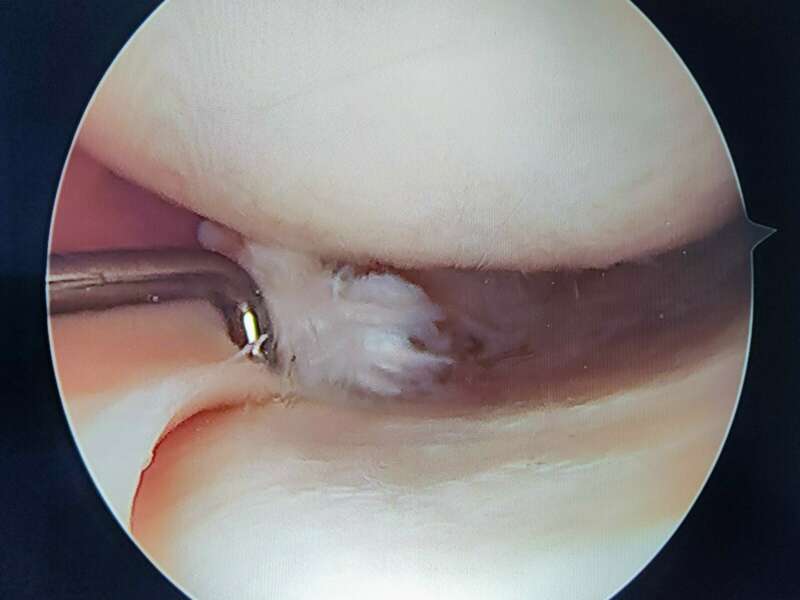

La plupart du temps, les lésions méniscales traumatiques sont traitées chirurgicalement. Deux gestes sont possibles : la réparation méniscale et la méniscectomie. Ces deux interventions sont réalisées au cours d’une arthroscopie et ont des indications spécifiques à chacune.

Nous différencions trois zones. Une « rouge-rouge », au contact de la capsule articulaire (en périphérie), bien vascularisée, qui peut être suturée, surtout chez le jeune. Une zone « rouge-blanche » médiane, qui est moins cicatrisable, car moins bien vascularisé. Et une zone « blanche-blanche » (en profondeur), faiblement vascularisée, et par conséquent rarement suturée.